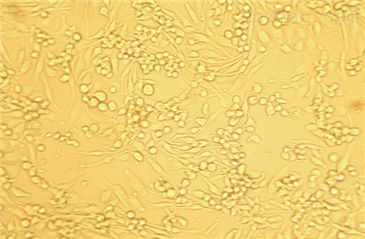

5)细胞生长方式:呈鹅卵石样,不规则细胞,贴壁培养。